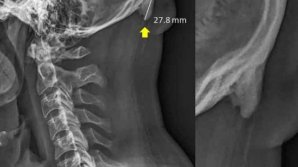

SEMNAL DE ALARMĂ: Tinerii dezvoltă oase asemănătoare unor coarne, din cauza utilizării telefonului mobil